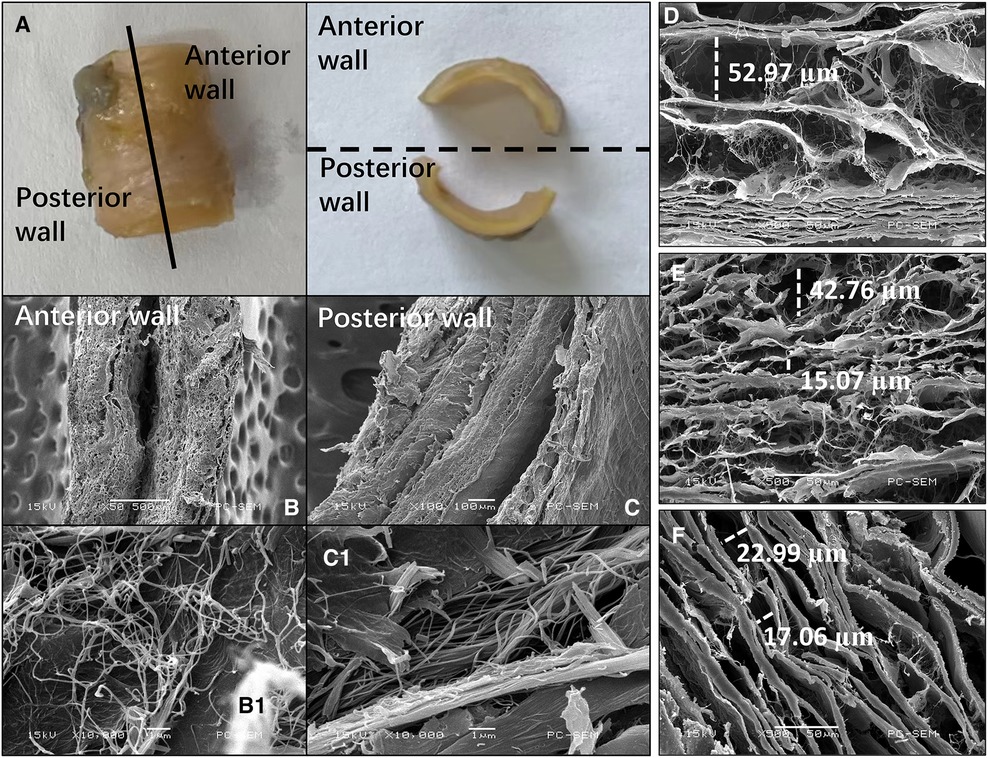

Results: A total of 124 patients with SMAS and 61 patients with SMAD were included. Most SMASs were circumferentially distributed at the SMA root, whereas the origin of most SMADs was located on the anterior wall of the curved segment of the SMA. Vortex, higher turbulent kinetic energy (TKE), and lower wall shear stress (WSS) were observed near plaques; higher TKE and WSS were seen near dissection origins. The intima in the SMA root (388.5 ± 202.3 µm) was thicker than in the curved (243.8 ± 100.5 µm; p = .007) and distal (183.7 ± 88.0 µm; p < .001) segments. The media in the anterior wall (353.1 ± 37.6 µm) was thinner than that in the posterior wall (473.7 ± 142.8 µm; p = .02) in the curved segment of the SMA. The gaps in the lamellar structure in the SMA root were larger than in the curved and distal segments. The collagen microstructure was more substantially disturbed in the anterior wall than in the posterior wall in the curved segment of the SMA.

Each segment of the SMA was separated into anterior and posterior walls (Figure 7A). The gaps in the lamellar structure were larger in the SMA root than in the curved and distal segments (Figures 7D–F). In the curved segment, the delamination of each layer was not obvious in the anterior wall (Figure 7B), whereas a clear 3-layer structure could be seen in the posterior wall (Figure 7C). Microstructure analysis of the collagen fibers between the intima and media showed that the fibers in the anterior wall were of uneven thickness and were interlaced in a disorderly manner (Figure 7B1), whereas the fibers in the posterior wall had a uniform thickness, with all fibers generally positioned in the same direction (Figure 7C1). In the other two segments of the SMA, the above phenomenon was not obvious.

Figure 7. Images of the superior mesenteric artery (SMA) wall from an SMA specimen. (A) SMA specimen divided into anterior and posterior walls. (B,C) Cross-sectional scanning electron microscopy images of the anterior (B) and posterior (C) wall of the curved segment of the SMA. (B1, C1) Collagen microstructure skeletonization images showing the area between the intima and media of the anterior (B1) and posterior (C1) walls in the curved segment of the SMA. (D–F) Scanning electron microscopy images showing the lamellar structure between the intima and media in the root (D), curved segment (E), and distal segment (F) of the SMA. The widths of some gaps have been marked.

In the curved segment of the SMA, the anterior wall was found to be significantly thinner than the posterior wall. Previous research has shown that thinning of the anterior wall is closely related to the loss of smooth muscle cells (23). The current study also demonstrated translamellar mucoid extracellular matrix accumulation breaking across laminar units in the anterior wall. This reduces the strength of the wall and is therefore considered an important index for the evaluation of medial degeneration (24). In our study, the microstructure of collagen fibers was also found to be substantially different between the anterior and posterior walls; the collagen fibers in the anterior wall had more cross-kinking and were of uneven thickness, whereas the collagen fibers in the posterior wall were generally uniform in thickness and direction. Previous research has shown that there are more cross-linked collagen fibers in the wall of aneurysms than in healthy arteries, and an increase in cross-linking reflects weakening of the renewal ability of collagen fibers (25, 26). In the extracellular matrix, collagen fibers provide resistance to dissection and rupture (23), and so weakness in these fibers can allow for the occurrence of SMAD.